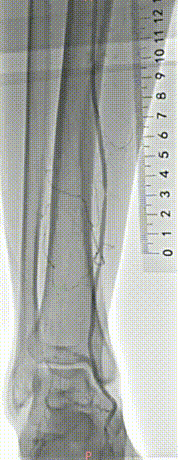

▲股浅、腘、胫后动脉经POBA+5*300 先瑞达DCB球囊扩张。

▲治疗完毕,最终造影结果,股浅动脉局部非限流性夹层,支架内、膝下流出道血流速满意。